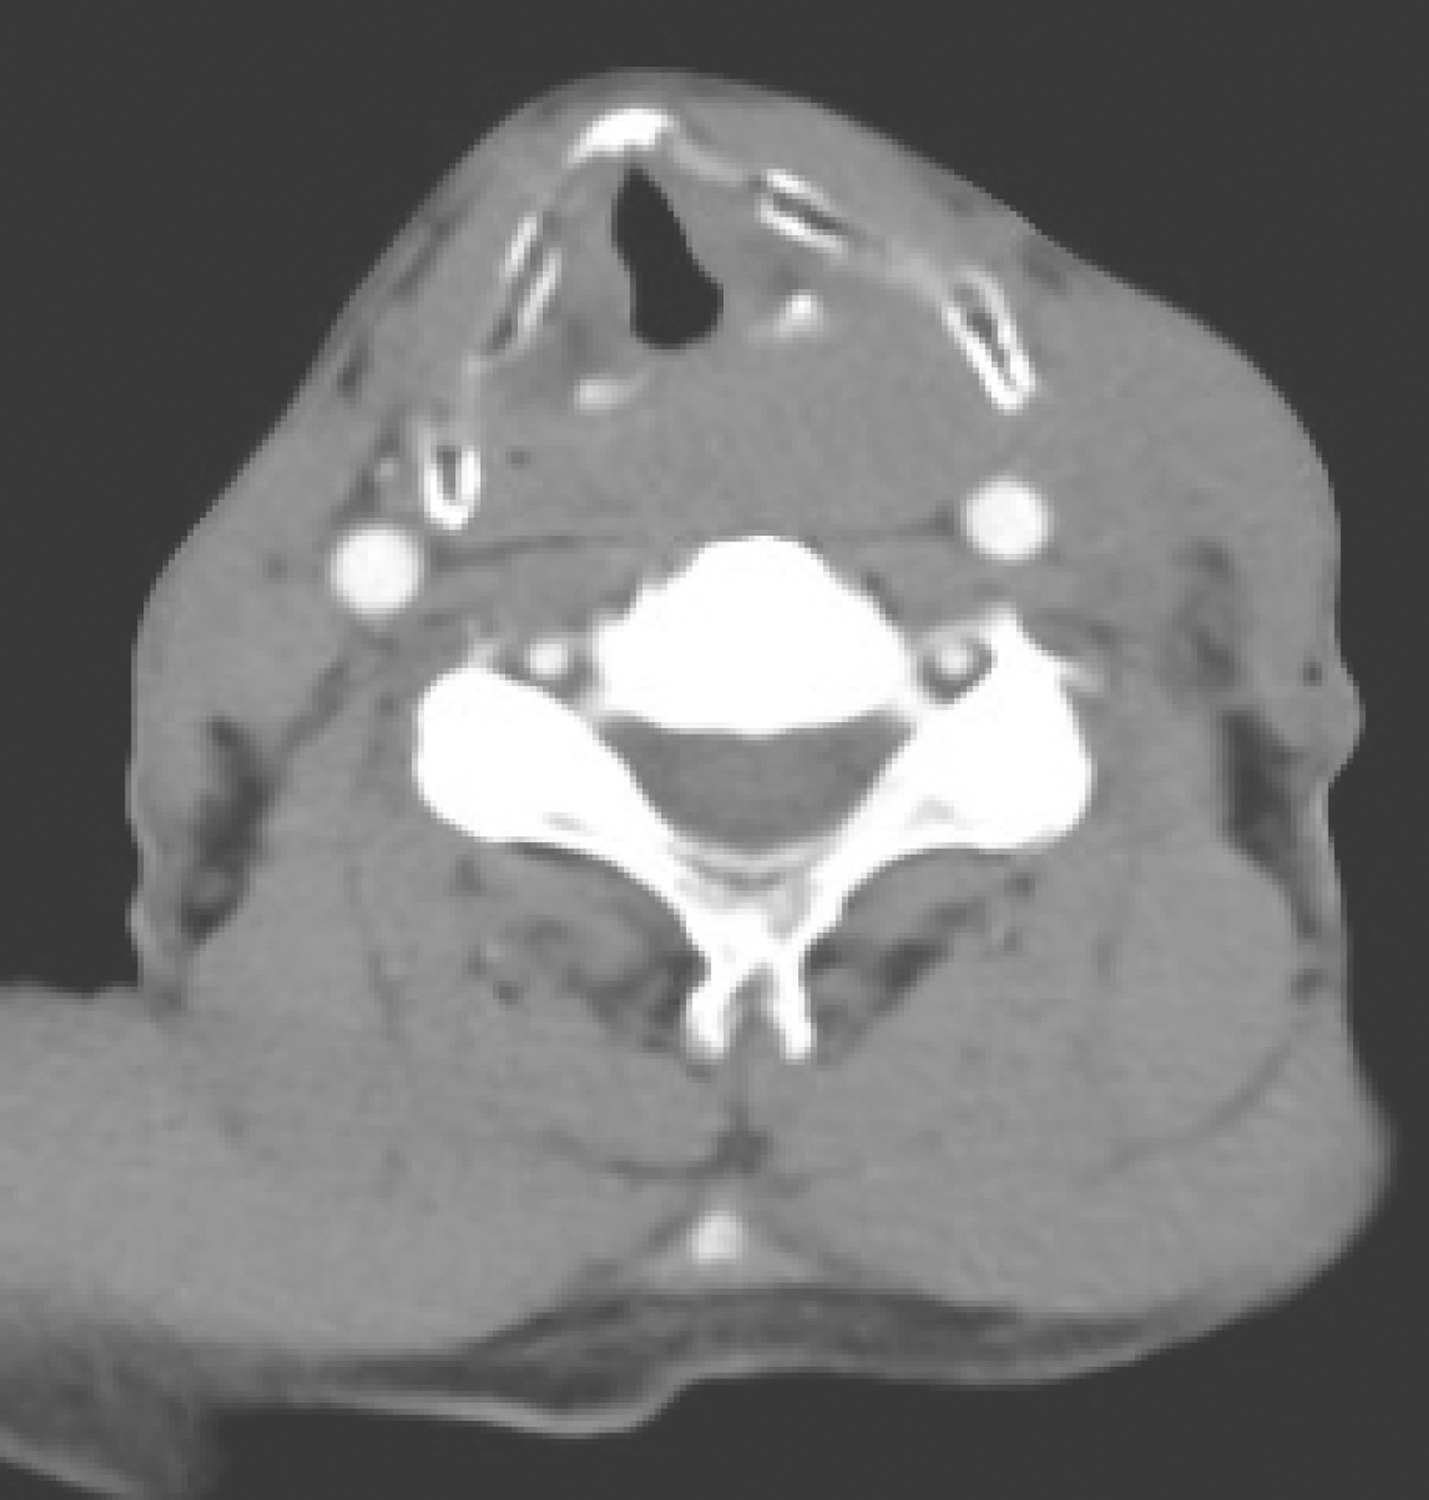

双侧杓会厌皱襞、环后可见软组织密度肿物,累及颈段食管(图1),增强扫描呈轻度不均质强化,左侧颈部胸锁乳突肌内侧肿大淋巴结影,密度欠均匀,边界不清,大者约3cm×2.5cm,增强扫描呈轻度强化(图2)。

图1颈胸部增强CT示双侧杓会厌皱襞、环后可见软组织密度肿物